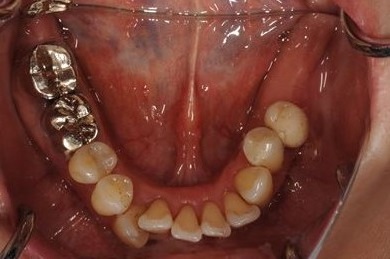

インプラントの症例写真 IMPLANT

インプラント治療+ソケットリフト+GBR

| 性別/年齢 | 女性 / 55歳 | ||||||||||||||||||||||||||||||||

| 主訴 | 奥歯が3本抜歯されてしまったあとにインプラントを入れたい。 | ||||||||||||||||||||||||||||||||

| 治療内容 | インプラント3本(ソケットリフト、GBR)、ハイブリッドセラミック3本 | ||||||||||||||||||||||||||||||||

| 総治療費 | 1,295,300円 | ||||||||||||||||||||||||||||||||

| 治療期間 | 8ヶ月 |